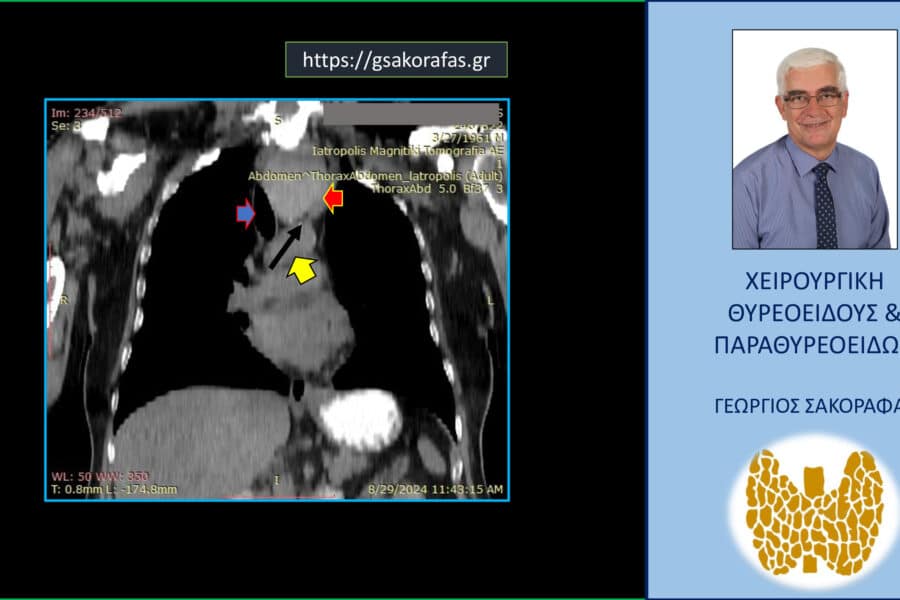

Όζοι θυρεοειδούς και συμπληρωματική θυρεοειδεκτομή (completion thyroidectomy) – με αφορμή ασθενή μας Παρουσίαση ασθενούς Αιτία…